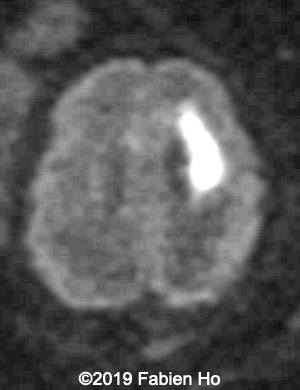

Images 4-11, fetal brain MRI at 28 weeks: the left frontal lesion hence shows DWI hyperintensity, with T2* and T1 peripheral hyperintensity: ischemia with peripheral subacute hemorrhage. Note also that there is an associated blood clot in the left lateral ventricle. There is no obvious mass effect, nor peripheral edema. All these findin>gs are very suggestive of a clastic lesion.

Axial DWI (diffusion weighted imaging): DWI is sensitive to cytotoxic cell edema, found in brain ischemia, among other things.

10

11

Our diagnosis was hence fetal stroke: probably ischemic stroke with secondary hemorrhagic transformation (hemorrhagic stroke could also be a possibility although the absence of mass effect and central lucency without hemorrhagic signal make this hypothesis less likely). Besides, in most pediatric and fetal clastic lesions, hemorrhage and ischemia are associated.